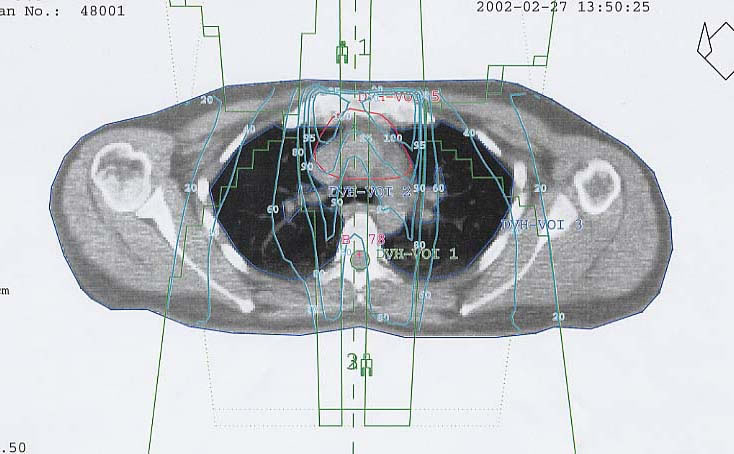

Schilddrüsenkarzinom: Bestrahlungsplan